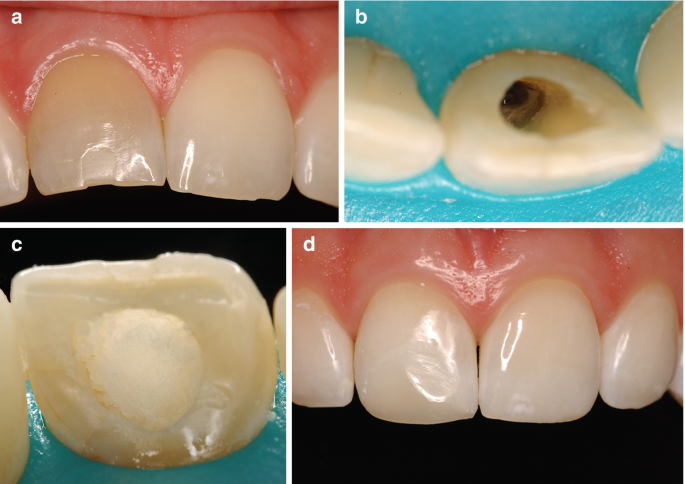

- معاینه و بررسی اولیه: دندانپزشک دندان را معاینه کرده، علت تغییر رنگ را تشخیص میدهد و از سلامت ریشه اطمینان حاصل میکند. ممکن است رادیوگرافی نیز انجام شود.

- ایزولاسیون دندان: برای محافظت از لثه و دندانهای مجاور، دندان مورد نظر با رابردم ایزوله میشود.

- تخلیه مواد پرکننده: مقدار کمی از مواد پرکننده کانال ریشه در قسمت تاج دندان برداشته میشود تا فضای کافی برای ماده بلیچینگ ایجاد شود.

- قرار دادن ماده بلیچینگ: ماده بلیچینگ با دقت در داخل حفره دندان قرار میگیرد.

- پانسمان موقت: حفره دندان با یک پانسمان موقت بسته میشود تا ماده بلیچینگ عمل کند.

- پر کردن دائمی: پس از رسیدن به رنگ مطلوب، ماده بلیچینگ خارج شده و حفره دندان با مواد پرکننده دائمی ترمیم میشود.

- پولیش نهایی: در نهایت، دندان پولیش میشود تا سطحی صاف و براق داشته باشد.